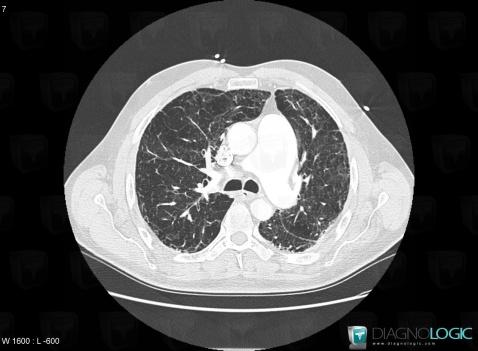

Centrilobular emphysema, Pulmonary parenchyma, CT

Here is the specific information in the key image above:

- Diagnosis Centrilobular emphysema (link to Emphysema), Location(s) Pulmonary parenchyma, with gamuts Multiple cystic lung lesions